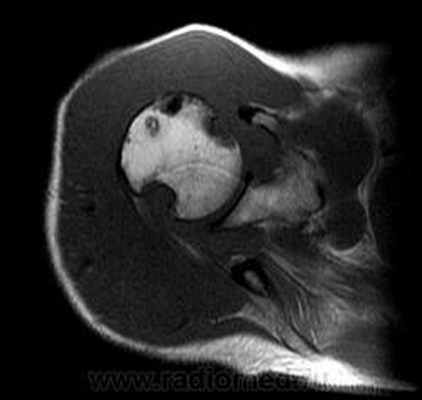

Пигментный виллёзонодулярный синовит - редкое заболевание с доброкачественным течением, характеризующееся пролиферативными изменениями синовиальной оболочки, отложением гемосидерина, образованием ворсинок, паннуса. Две разновидности: виллёзонодулярный бурсит и виллёзонодулярный тендосиновит. Частота - 2 на I 000 000. Преобладающий возраст • Виллёзонодулярный бурсит - 30-40 лет • Виллёзонодулярный тендосиновит -50-60 лет. Преобладающий пол - женский. Этиология. В 30% случаев развитию синовита предшествует травма сустава. Патоморфология. Пролиферация клеток синовиальных оболочек с образованием узлов, содержащих клеточный инфильтрат из фибробластов, лимфоцитов, макрофагов с жировыми включениями. Клиническая картина • Виллёзонодулярный бурсит -моноартрит. Чаще всего (80% случаев) поражается коленный сустав, реже - (с убывающей частотой) тазобедренный, голеностопный и плечевой суставы • Виллёзонодулярный тендосиновит - образование узелков в мышечных сухожилиях и связках сустава. Лабораторные исследования • Увеличение СОЭ • Синовиальная жидкость ксантохромная, с примесью крови • Биопсия синовиальной оболочки: узловая пролиферация, гемосидероз, инфильтрация мононуклеарными клетками. Рентгенологическое исследование • Остеопороз и наличие остеофитов нехарактерны • Артропневмография: множественные округлые дефекты наполнения синовиальной полости, обусловленные наличием узлов или гипертрофированных ворсинок синовиальной оболочки • МРТ - выявление гемосидерина и жировых включений. Артроскопия • Суставной хрящ приобретает коричневую окраску вследствие гемосидероза • Различной величины узлы коричневого цвета. Дифференциальный диагноз • Виллёзонодулярный бурсит • Липома - в аспиратах отсутствует ксантохромная жидкость • Остеоартроз - кисты возникают только на суставных поверхностях, подвергающихся нагрузке, тогда как при пигментном виллёзонодулярном синовите они образуются на всех суставных поверхностях. Остеофи-ты, напротив, более типичны для остеоартроза • Воспалительные арт-ропатии, дебютирующие моноартритом, - ревматоидный артрит, туберкулёзный артрит, анкилозирующий спондилоартрит и др. • Виллёзонодулярный тендосиновит - панглии (околосухожильные кисты): аспираты ганглиев содержат гелеподобную жидкость. Лечение хирургическое • Виллёзонодулярный бурсит • Тотальное иссечение синовиальной оболочки, вероятность рецидива заболевания составляет 25-40% • Лучевая терапия • Виллёзонодулярный тендосиновит - иссечение кист. Синоним. Синовит геморрагический МКБ. М12.2 Ворсинчато-узелковый (виллонодулярный) синовит (пигментный)

Рис. 5. А. Артроскопическая картина коленного сустава, при пигментно-ворсинчатом узелковом синовите (ПВУС). Б. После артротомии сустава.

В. Состояние хрящевого покрова. Хрящевой покров бедра и надколенника пропитан гемосидерином.